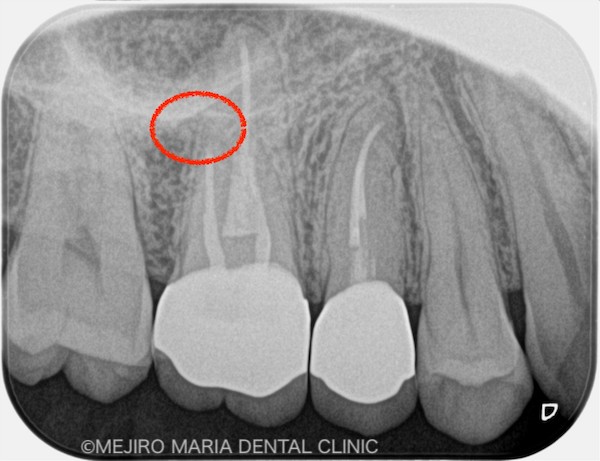

患者様は、「数年前に虫歯治療した歯の、根元が腫れた」という主訴で来院されました。かかりつけ医に相談したところ、痛くないのであれば様子を見るようにと指示されましたが、不安を抱いて当院へお越しになりました。

右上の歯を確認したとろ、当該部位にはフィステル(瘻孔)が確認でき、フィステルより造影してみると、右上6番の歯の根尖部付近から、排膿されていることがわかりました(写真の赤矢印)。フィステル以外に痛みなどの所見は見当たらないものの、「根尖性歯周炎」と診断し、治療を開始しました。